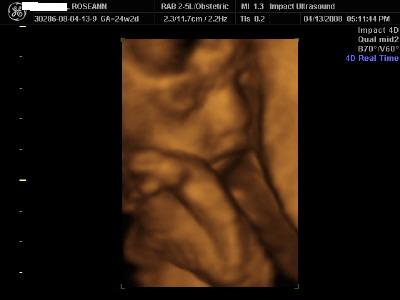

Here are 3D pics of Seamus Finn I was a little over 24 weeks when I had them done yesterday. i went to Impact Technologies in East Meadow. They were great. We bought all the grandparents and they got to sit on couches and they projected the sonogram on a big movie screen on the wall! We went out to dinner afterwards and our parents surprised us and told us they are buying all 4 pieces of our furniture!! We are very excited

The first pic is my absolute favorite. He didnt want to be bothered much. He kept turning his @ss to us and we had to jiggle my belly to get him to flip!! And the tech said that he definately has hair! He showed us in 1 of the pics the squiggly lines! Image Attachment(s):